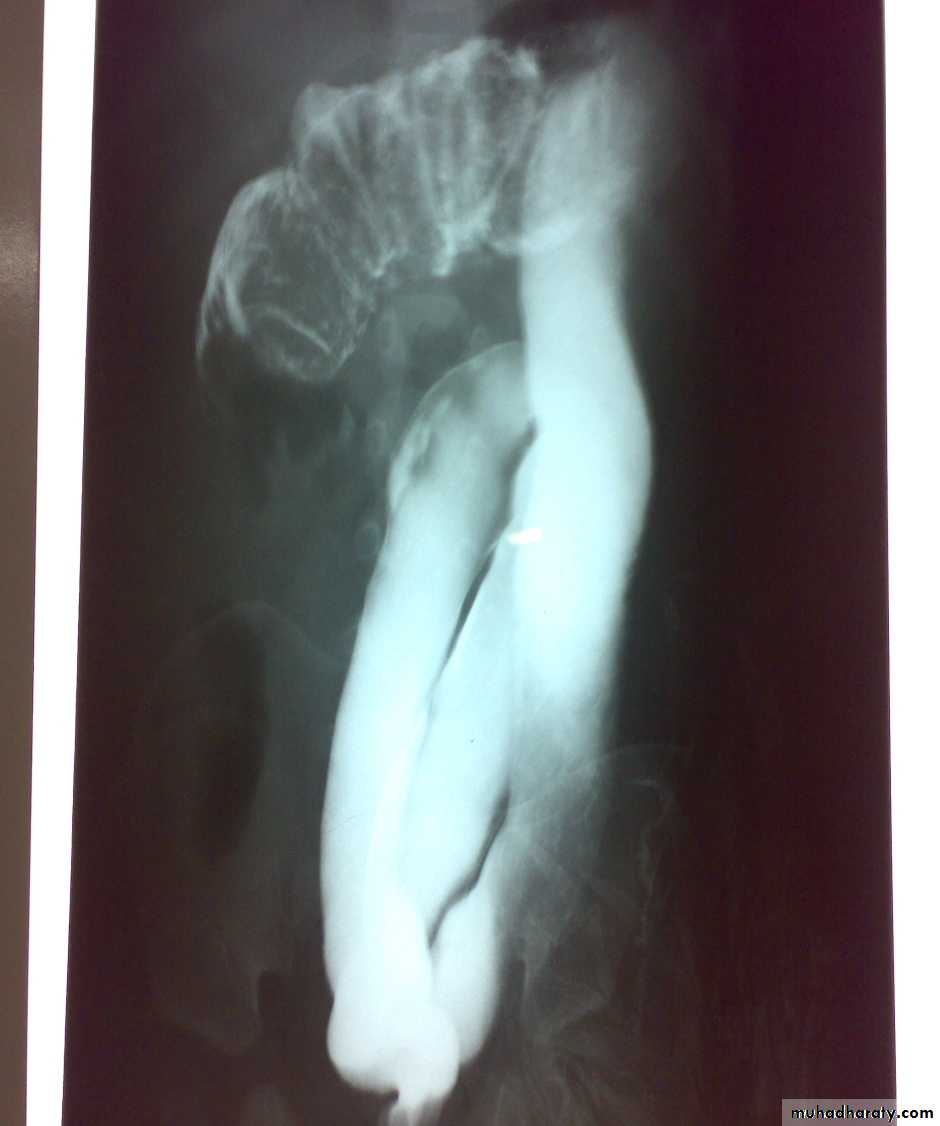

Oesophageal Atresia and Tracheo-Oesophageal Fistula,